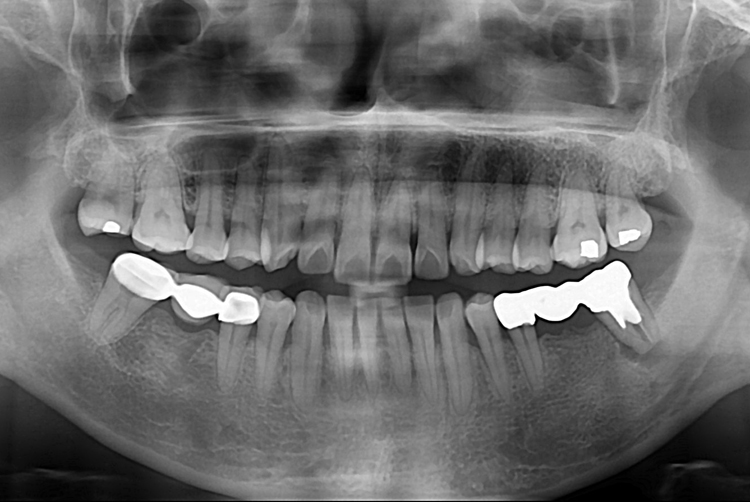

[임플란트] 어금니 임플란트

치료후 : 2019-08-27

세종치과는 많은 환자와 다양한 케이스를 바탕으로

항상 편안한 임플란트 수술을 제공하고자 노력하고,

오래동안 튼튼히 쓸 수 있는 임플란트 수술을 가장 큰 목표로 삼고 있습니다.